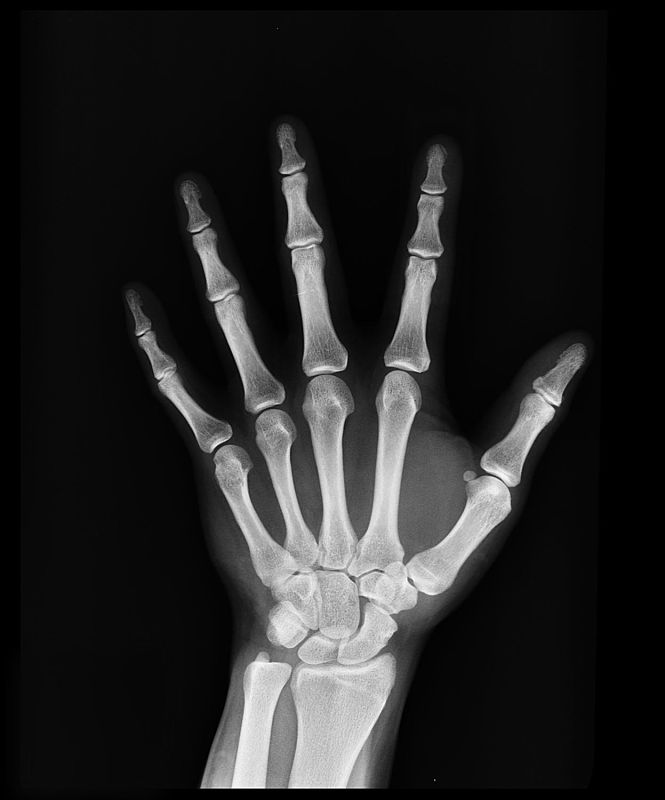

La hipofosfatasia en adultos conlleva una pérdida de mineralización que da lugar a fracturas recurrentes, fracturas femorales, antecedentes de raquitismo y dolor musculoesquelético, además de afecciones dentales. En el caso de los niños es mucho más grave, provocando incluso la muerte prematura a los pocos días de vida, daños cerebrales y problemas respiratorios.